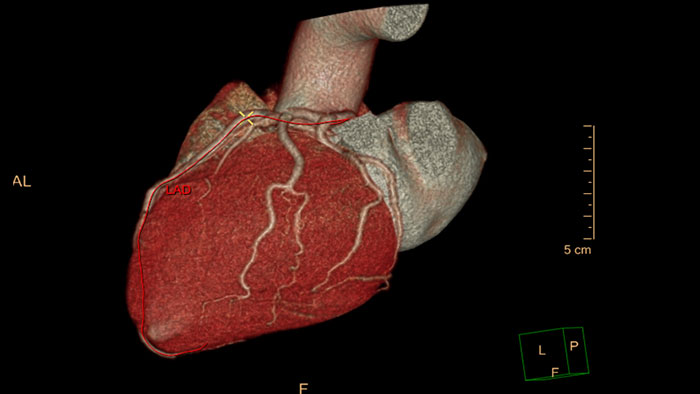

Comprehensive Cardiac Analysis (CCA)

CT Comprehensive Cardiac Analysis (CCA)

Comprehensive cardiac analysis

Designed to assist the user in viewing, analyzing and quantifying dedicated Cardiac CT Angiograms, mainly for coronary arteries analysis on Coronaries CT Angiogram (CCTA) data.

comprehensive cardiac analysis thumbnail

Benefits

• Cardiac function measurements based on automatic 3D model-based whole-heart segmentation.

• Automatic extraction and visualization of the coronary tree.

• The user can edit and modify the segmentation and the derived parameters.